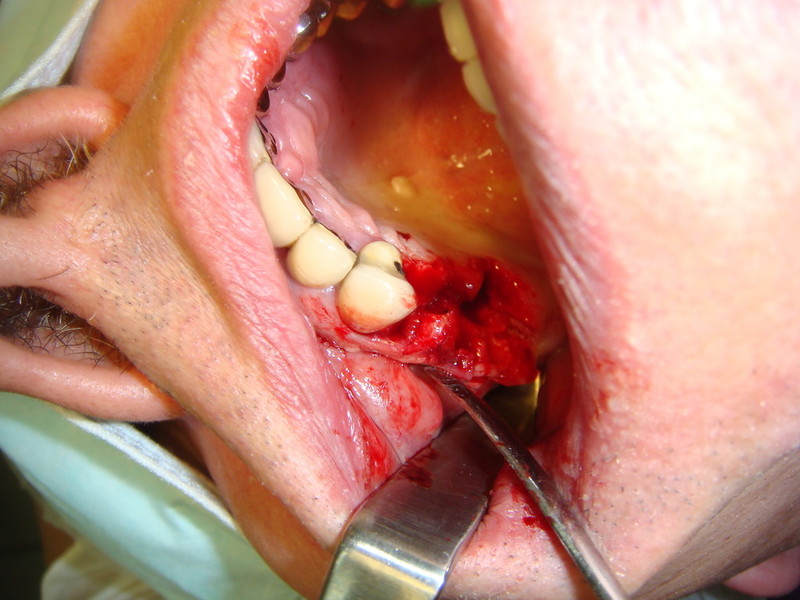

Impianti post-estrattivi complessi con innesto osseo

Impianti Post-estrattivi con innesto di osso e tessuto epitelio-connettivale